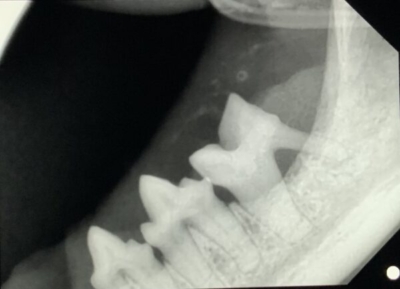

下顎のレントゲン写真

すでに歯周病を併発して黄色斜線部位は骨が溶けてしまっている。通常、口内炎でなくとも抜歯対象となる。